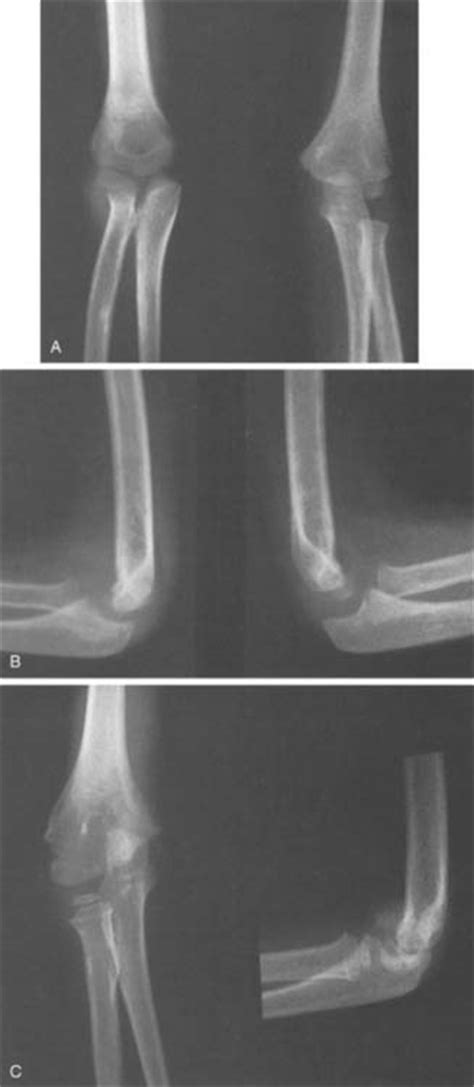

Physeal Fractures of the Elbow | Musculoskeletal Key

Physeal Fractures of the Elbow | Musculoskeletal Key from musculoskeletalkey.com

Such injuries occur in a variety of sports due to substantial stress on the ulna and repetitive excessive rotation of the forearm. Thankfully, stress fractures in the large bones of the body are rare. Such injuries occur in a variety of sports due to substantial stress on the ulna and repetitive excessive rotation of the forearm. Stress fracture of the ulna due to the use of crutches is rare. They are very thin cracks in the bone caused by overuse. The image belongs to a 40 years old man who sustained trauma to left. A stress fracture is usually the result of repeated trauma or overuse that occurs when muscles become fatigued or overloaded. Stress fractures are common injuries in athletes and military recruits. Stress fractures result from recurrent and repetitive loading of bone. Stress fractures can cause significant discomfort, especially in areas of. Stress fractures are not full thickness breaks (although without correct management they. Stress fractures can also develop from normal use of a bone that's weakened by a condition such as osteoporosis. Forearm fractures involve fracture of shaft of ulna or radius or both bones. This can happen from repetitive trauma and is commonly seen in. Sometimes, it is also referred to as fissure fracture. Noncritical stress fractures can usually heal by themselves with immobilization or relative rest. They are a relatively common overuse.